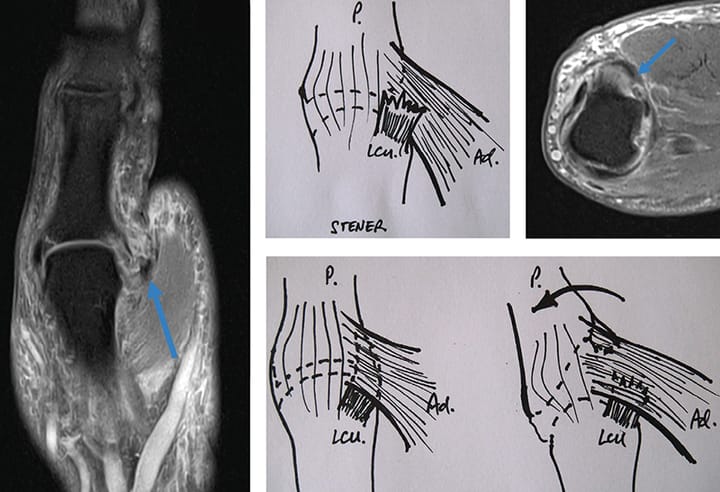

Traumatologie - Orthopédie Proposition d'un arbre décisionnel aidant au diagnostic kinésithérapique différentiel des pathologies de la face médiale et du pivot central du genou